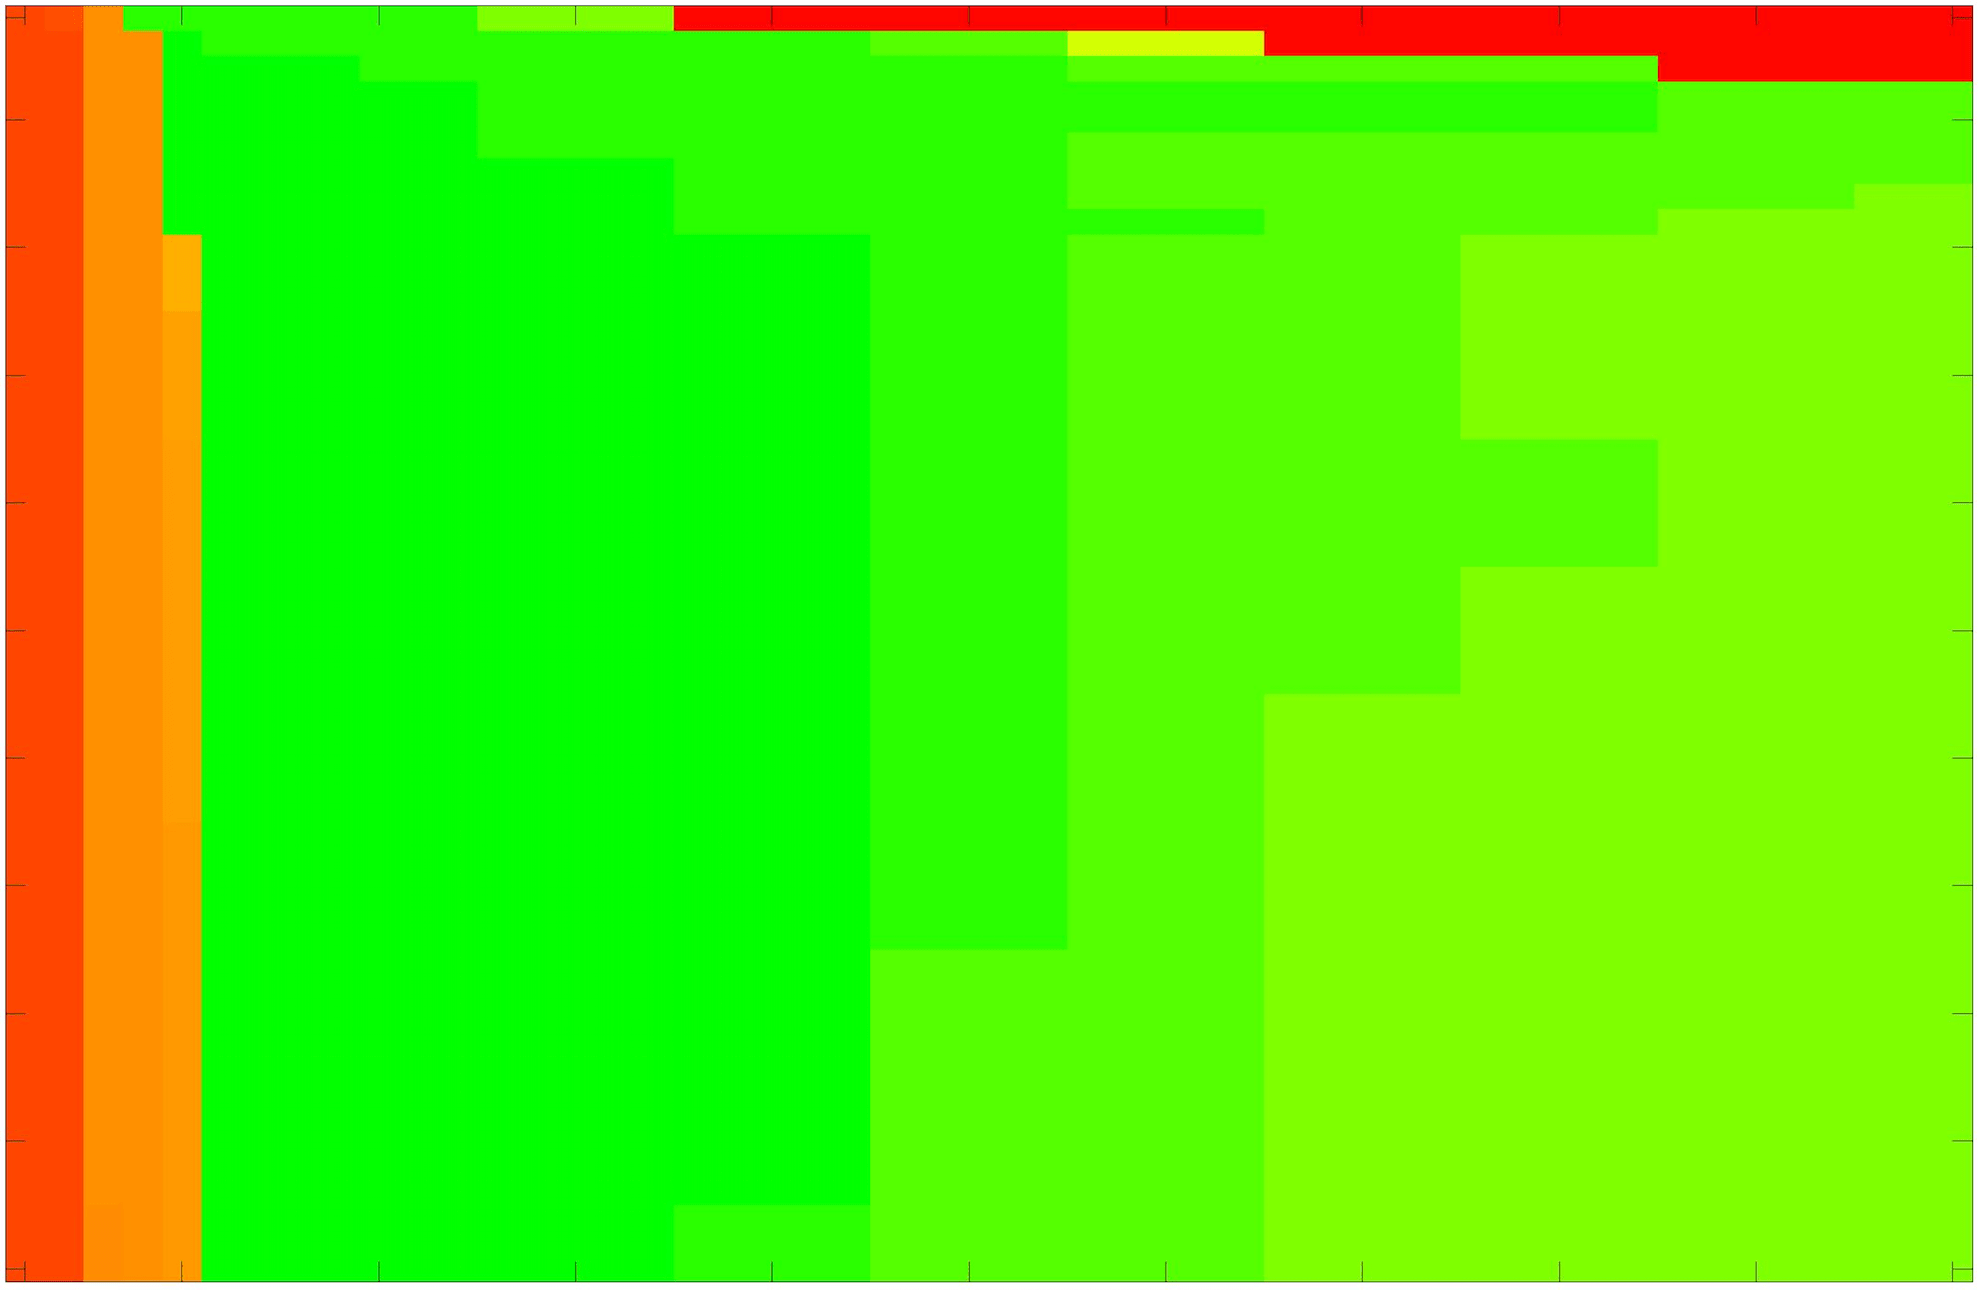

where refers to the number of points in the enclosed region. This takes values in the range , with higher TC values indicating a more accurate segmentation. In the following we will represent accuracy visually from red () to green (), with the intermediate scaling of colours used shown in Fig. 8. This will be particularly relevant in §7.2.

The TC values for the parameter sets are presented as heatmaps in Figs. 11–13. A heatmap is a convenient way to display accuracy results for hundreds of tests concisely. In Fig. 9 we give an example heatmap with the same axes used for those in Figs. 11–13. For each of the combinations of parameter values we give the TC value of the segmentation result and represent it by the appropriate colour. The corresponding colour scale is shown in Fig. 8. Qualitatively, the more green areas of the heatmap the more accurate the model is for a wider set of parameters. Example results for Test Image 5 when varying (with ) for the proposed model are given in Fig. 10. Here it can be seen what each accuracy result corresponds to visually.

Note. The axes have been removed from the heatmaps in Figs. 11–13 for presentational clarity. However, to be explicit, the axes used in all heatmaps are the same as those in Fig. 9.

Synthetic Images. These results are presented in Fig. 11. For Test Images 1–2 we see poor parameter robustness from all competing models, except for GAV which performs reasonably well. However, the proposed model has minimal parameter sensitivity for these images, with good results achieved for almost every combination of values tested. For Test Image 3 all models have a reasonable parameter range (except for RSF), however the proposed model gives better quality results for a wider parameter range. The other models achieve reasonable results here as the foreground intensity of the ground truth is greater than the background , whereas for Test Images 1–2 they are equal . These results highlight the key advantage of the proposed model.

Real Images. In Fig 12 we present results for Test Images 4–6. Here, the proposed model performs in a similar way to its competitors because these images are more typical selective segmentation problems in the sense that there is a clear distinction between the foreground and background intensities. In particular, the values in each case are: Test Image 4 , Test Image 5 , and Test Image 6 . It can be seen that the proposed model is competitive compared to previous approaches. The performance is quite poor for Test Image 5, but is arguably still the best for this challenging case. In Fig. 13 we present results for Test Images 7–9. Here the proposed model outperforms previous approaches significantly for each image. This is mainly due to the type of image considered. Specifically, the true intensities are: Test Image 7 , Test Image 8 , and Test Image 9 . The proposed model is capable of achieving results where , with other models failing completely in these cases.